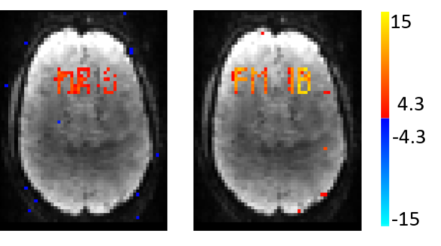

Figure 7 shows the Default Mode Network (DMN) regressor used for dual regression overlaid on the MNI atlas, as well as the z-stat dual regression outputs of the ground truth, kt-FASTER, L+S and PEAR for R=6.66. All maps are thresholded at and with color scale mapped between . The results for R=10, are shown in Fig. 8. The green ellipses in the images show regions where PEAR’s activation pattern is the most similar one to the ground truth. It can also be seen that while both k-t FASTER and PEAR provide reliable results for both R=6.66 and R=10, L+S is does not provide satisfactory results at the higher acceleration ratio of R=10.

Reconstruction results (R=10)

L+S k-t FASTER PEAR